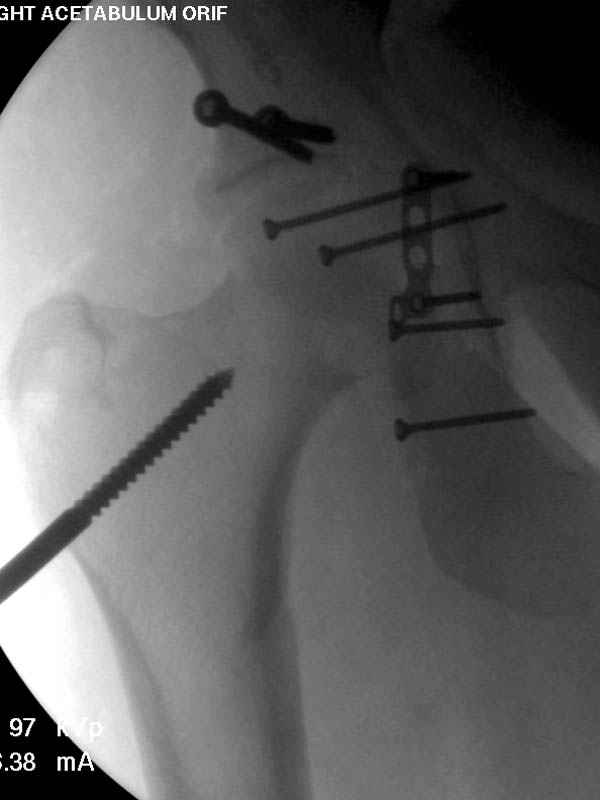

Прооперирован вчера на 13 день после поступления.

Больному 41 и из-за гемодинамической нестабильности в течение первых 7 дней был в реанимации под интубационной седацией.

Кроме перелома плеча у больного старый дистракционный перелом T12-L1 оперированный когда-то и кем-то, открытый перелом костей предплечья, который был прооперирован в ночь поступления, после I&D (хирургической обработки). Из-за разрыва селезенки при поступлении травма хирургами произведено удаление.

Дополнительно имеется перелом ацетабулума: задняя

колонна с полупоперечным переломом, и переломы костей лица.

На седьмой день зафиксирован перелом ацетабулума через задний доступ. Перед операцией для профилактики DVT, IVC фильтер, также получает Lovenox.

Извиняюсь за качества снимков, обычный больной в 300 фунтов, портативным ренген аппаратом не пробить.

Очень хорошаая работа, поздравляю! Хотелось бы увидеть снимок таза до операции. Каким образом и как долго предполагаете разгружать тазобедреннй сустав в дальнейшшем?

Отправитель: Evgueny Tchekashkine 30 Ноябрь 2007, 16:57

По возможности вышлите снимки, сканы таза до реконструкции, интраоперационные.

По снимку создается впечатление о высоком поперечном переломе, задней колонны, стенки; почему не пользовались *magic screw*?

По возможности вышлите снимки, сканы таза до

реконструкции, интраоперационные.

Там множество обычных 2.7 мм шурупов, потом идет фиксация основными пластинами.

Снимки здесь....